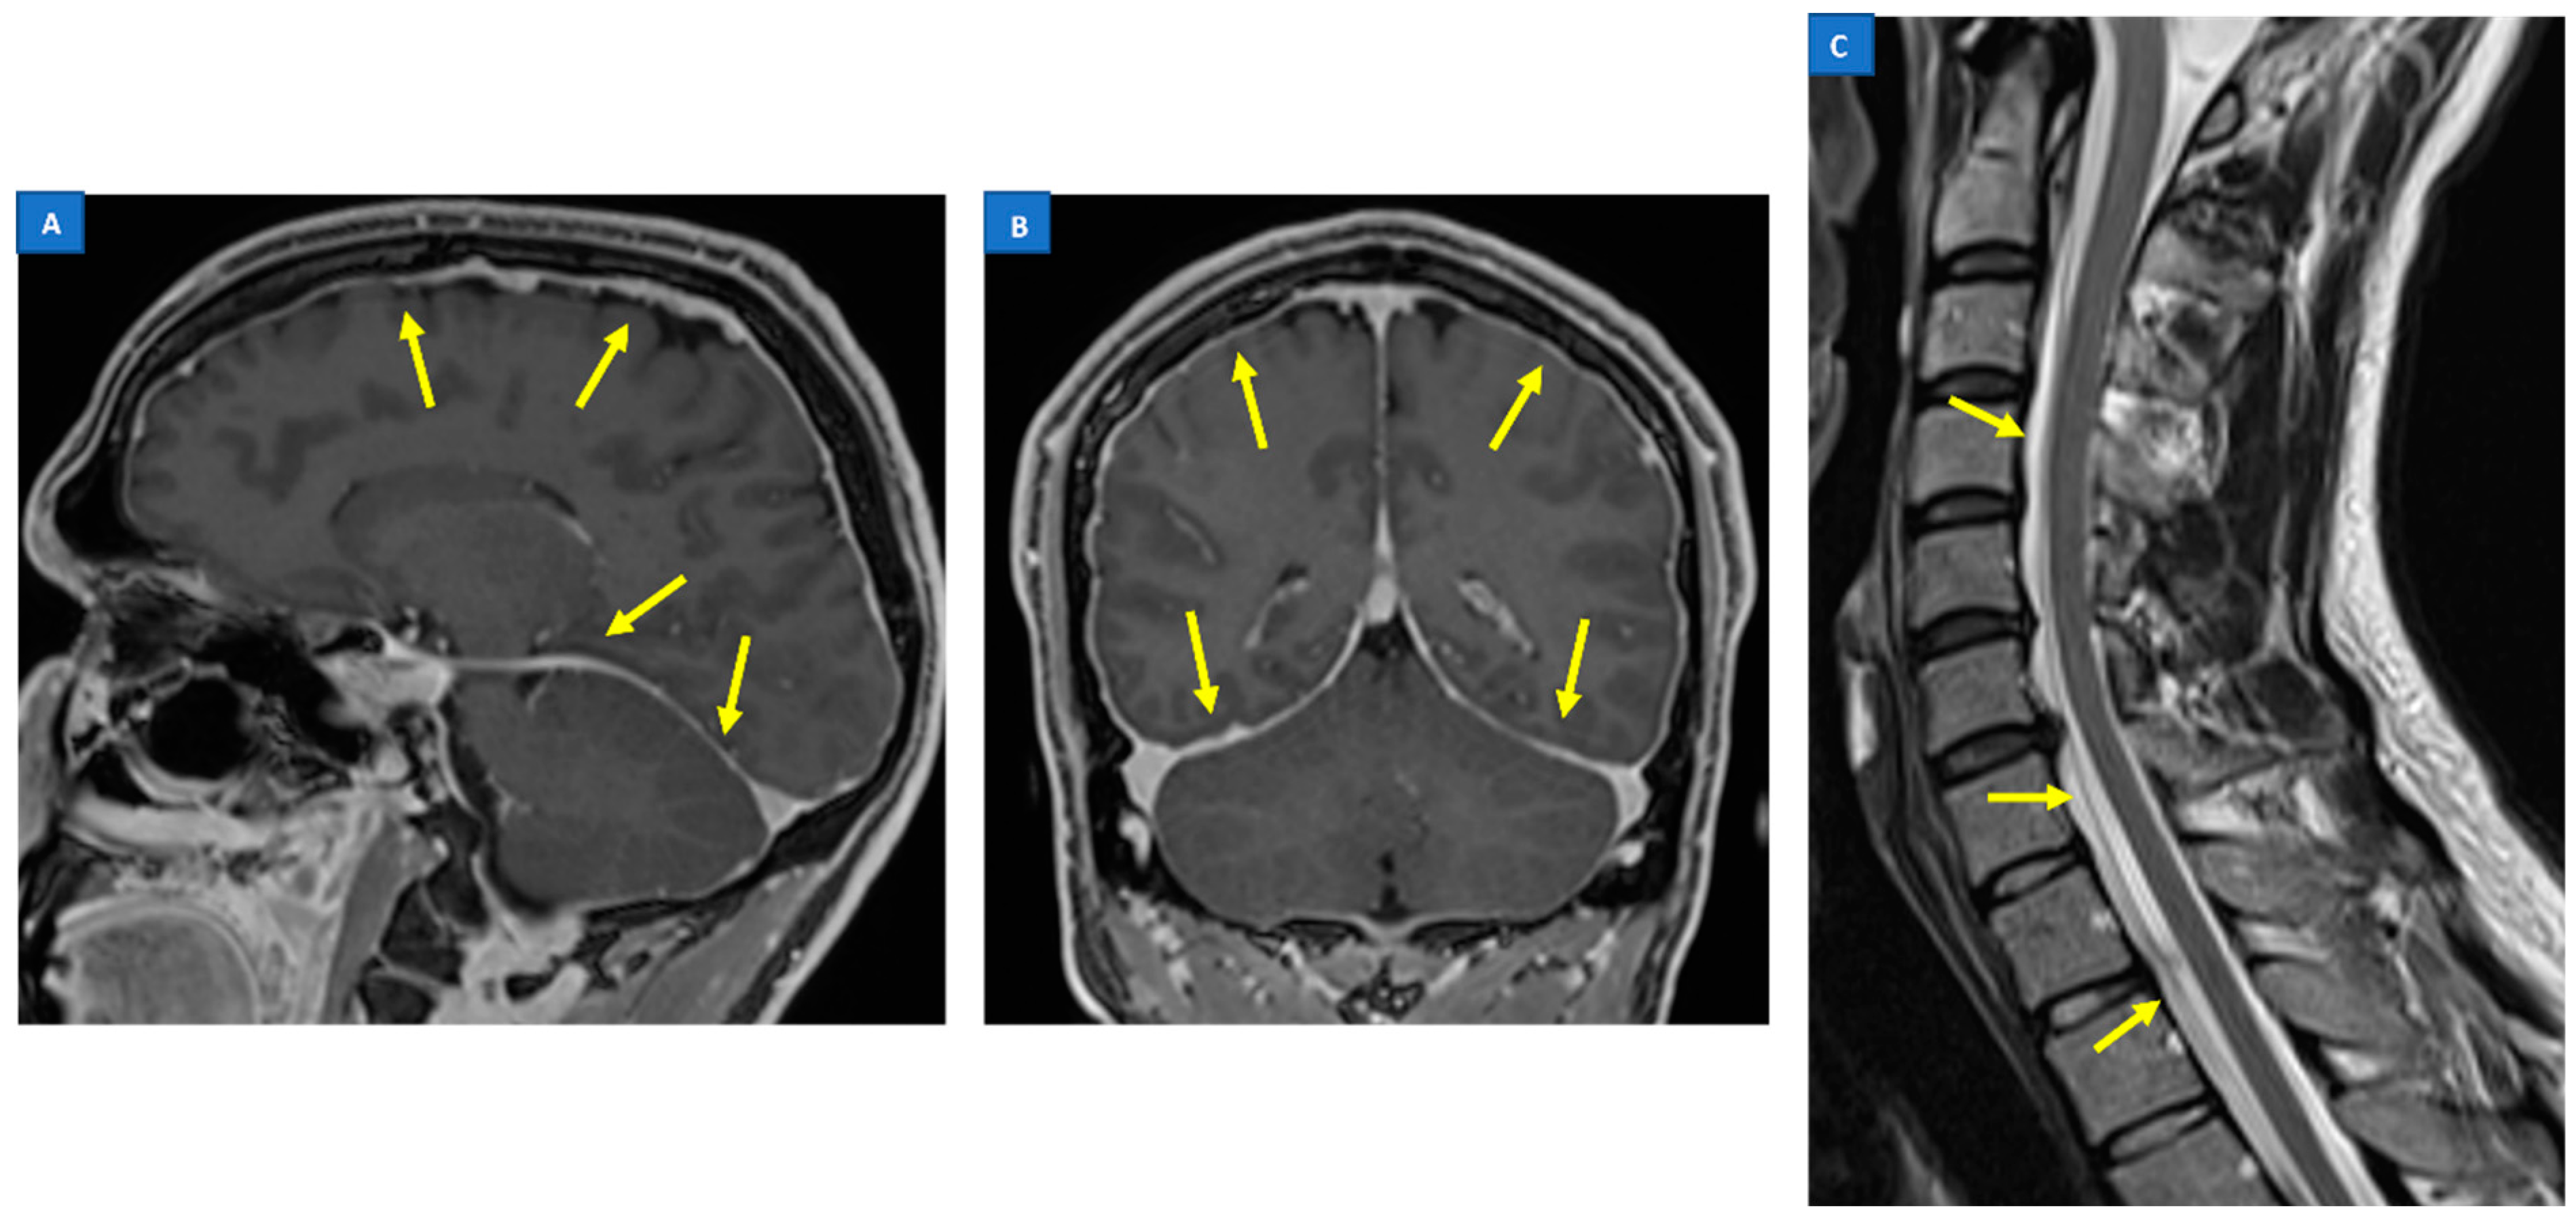

5.1. Head MRI

5.2. Spine MRI